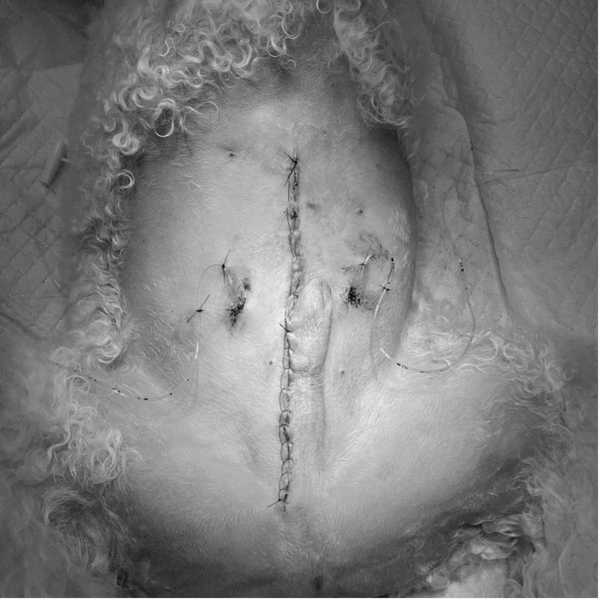

第24病日手術を実施した。胸骨剣状突起から恥骨前縁までの腹部正中切開を行い膀胱、前立腺へアプローチした。左右の尿管を確保し、膀胱移行部を露出後膀胱の近位で左右尿管を離断した。その後尿管にカテーテルを挿入し保持した。膀胱と前立腺、近位尿道を周囲脂肪組織から剥離し、前後膀胱動脈、前立腺動脈を処理し、最後に前立腺から十分距離を確保して尿道を骨盤腔内で結紮離断した。その後、左右尿管を腹壁に造瘻した孔を貫通させ、包皮外側の皮膚に縫合した。(図3,4)術後は左右尿管移設部位にカテーテルを留置し、入院管理を行った。入院5日目にカテーテルを抜去し、尿管移設部位からの尿排出を確認した後に退院となった。病理検査結果は、尿路上皮癌(移行上皮癌)完全切除であった。術後14日目に抜糸を行い、同日ラパチニブを開始した。またNSAIDsとしてフィロコキシブを併用した。 経過は良好であり、ラパチニブ開始から6ヵ月後に再発や転移が認められなかったことから、ラパチニブとフィロコキシブを中止し、現在術後約1年が経過するが再発や転移は認められていない。